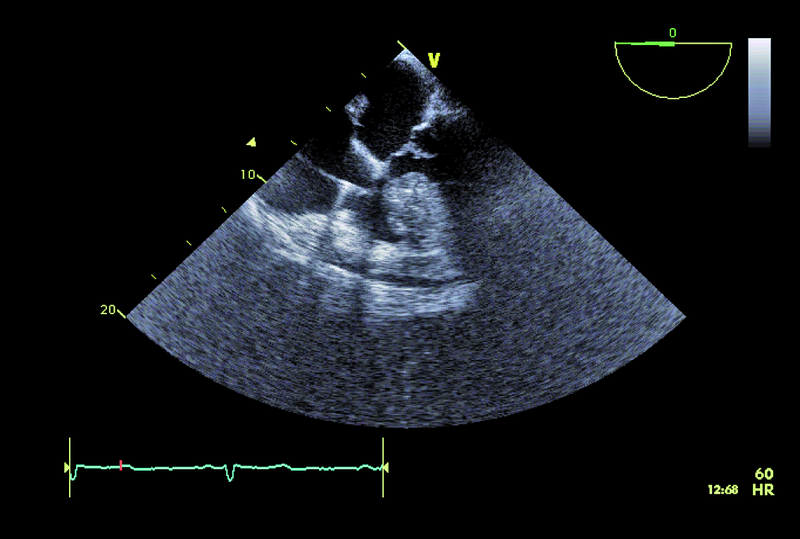

Kobieta, lat 55. Jakie patologie można rozpoznać na zamieszczonych rycinach?

1. Guz przegrody międzyprzedsionkowej (ryc. 1-3).

2. Mały ubytek przegrody międzyprzedsionkowej z przeciekiem lewo-prawym (ryc. 1-3).

4. Istotny przerost przegrody międzykomorowej (ryc. 1, 2, 5).